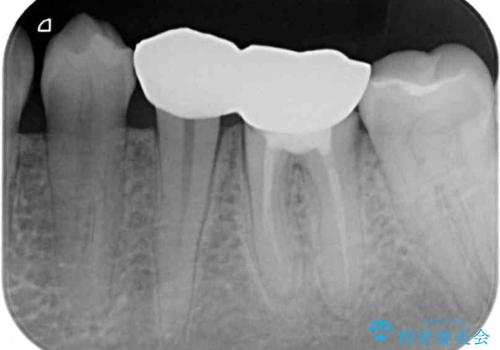

- クラウンを装着したばかりの歯の歯肉が腫れていることを気にして来院された患者様です。

むし歯がとても大きく、歯茎に歯の一部が埋もれてしまっているため、汚れが溜まりやすくなっている状態でした。

根歯の挺出(歯を引っ張り出す部分矯正)、歯周外科処置などを行った後、オールセラミッククラウンにて補綴することとしました。